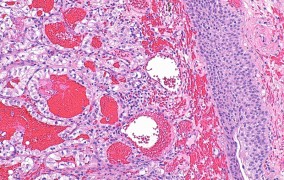

Com investimento da FAPESP, o Centro Avançado de Diagnóstico Molecular integra pesquisa básica e aplicada ao atendimento público; a partir da identificação de biomarcadores específicos, será possível detectar precocemente câncer e outras doenças